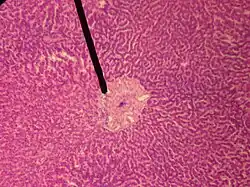

human central vein | |

In microanatomy, the central veins of liver (or central venules)[1] are veins found at the center of hepatic lobules (one vein at each lobule center).

They receive the blood mixed in the liver sinusoids and return it to circulation via the hepatic veins.[2]

The circulation of venous blood is: portal vein (which is formed by the joining of the superior mesenteric vein with the splenic vein) drains into the sinusoids of the liver, these all drain into the central veins of liver which drain into the hepatic vein to be returned to IVC.